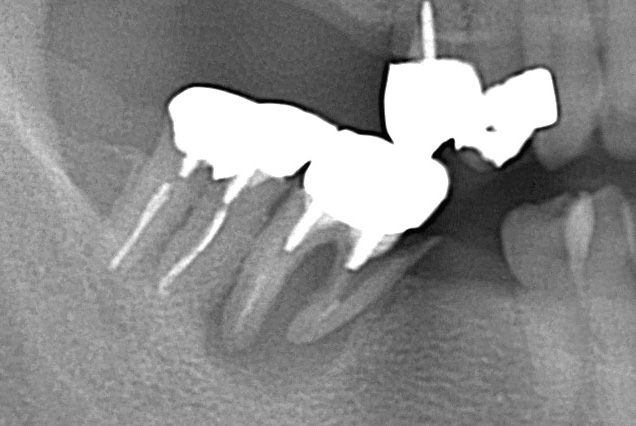

●被せ物で治した歯の場合

銀歯の縁などに虫歯が再発した程度なら、銀歯を外して虫歯を削り、再び銀歯で治します。

ところが、銀歯の内部で虫歯が広がっている場合や、銀歯が外れるほど大きな虫歯が再発した場合はそうはいきません。

根の治療をしてから被せ物をつける治療になりますので、治療期間も治療費も大きくなります。

虫歯が歯根の下あたりまで進んだ場合、抜歯しなければならないこともあります。

●土台を入れて被せた歯の場合

大きな虫歯の治療では、歯根にコアという土台をたててから被せ物を入れます。

このような歯に虫歯が再発した場合、歯根の周囲に膿がたまったりしていることがあります。

膿がたまっていたら、コアを取り除いてから根の治療を行い、被せ物を入れて治します。

コアを取り除いたのち、歯根にヒビが見つかった場合は抜歯になることもあります。